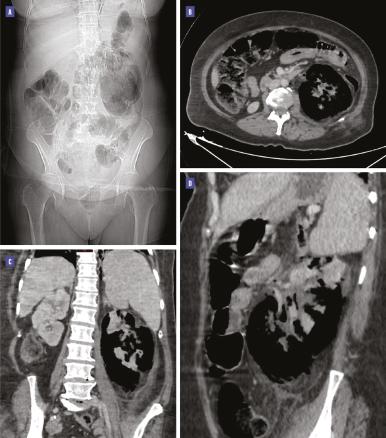

La tomodensitométrie (TDM) abdominopelvienne avec injection de produit de contraste montre la présence de gaz dans le parenchyme rénal gauche et la voie excrétrice supérieure avec une destruction parenchymateuse diffuse, et une extension des bulles au-delà du fascia de Gerota, sans obstacle visible, en rapport avec une pyélonéphrite emphysémateuse de stade 3B selon la classification de Huang et Tseng (figure).